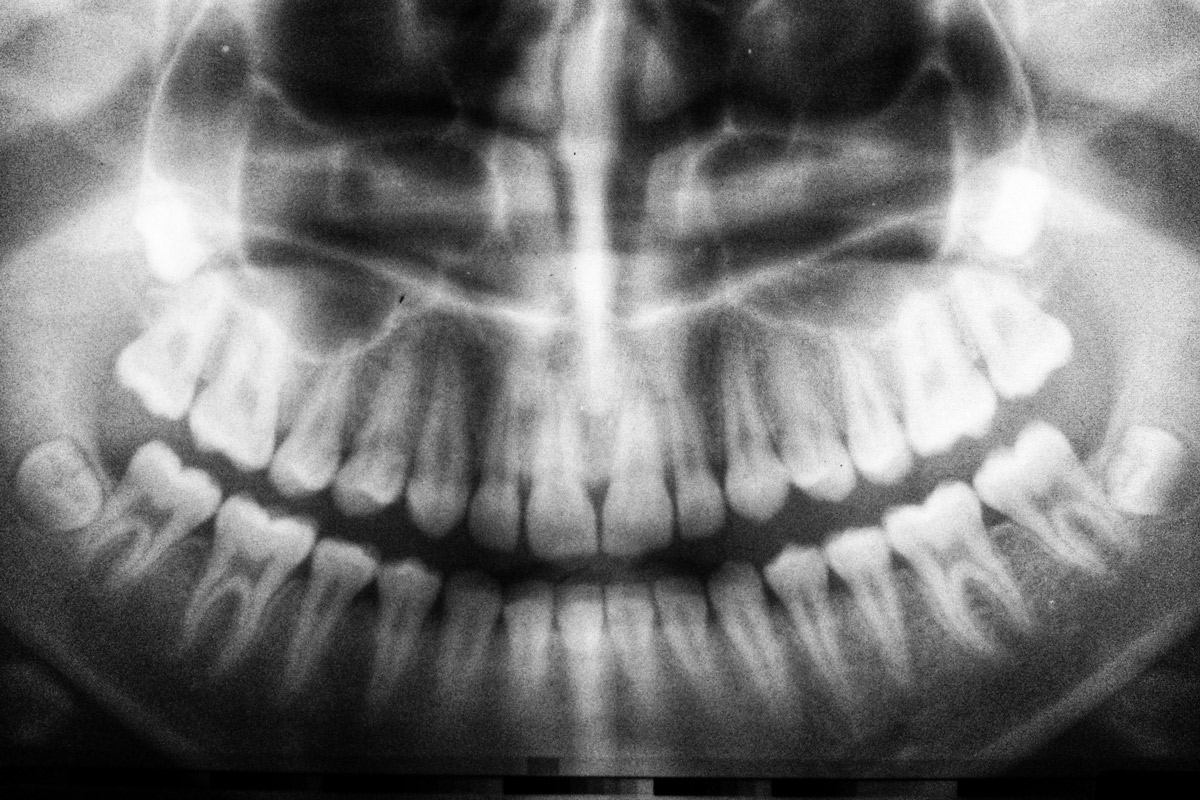

En primer lugar, realizará una exploración y una radiografía de nuestra boca para conocer el estado actual de las muelas del juicio. Entonces aconsejará si se debe realizar la extracción.